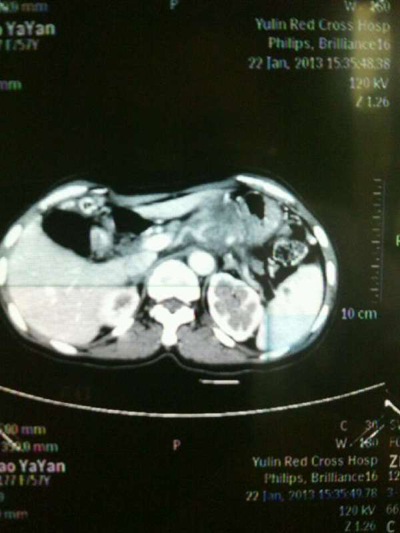

我院肝胆外科主治医师张洪昌医生介绍,赵大妈患上的是中晚期胰体尾肿瘤,瘤体很大,毗邻腹腔、肝脏、肠系膜、肾等多个器官重要血管,手术难度较大,风险极高。由于胰腺和胃的关系密切,所以引发了强烈的胃痛。

肝胆外科副主任医师韦杨年认为,赵大妈这种情况适合做肿瘤的根治性切除,能够将生存时间由3个月延长至两年左右。2月5日,在中南大学湘雅医院卫生部肝胆肠外科研究中心李年丰教授的指导下,韦医生为赵大妈实施了“胰体尾联合脾脏切除,腹主动脉淋巴结清扫术”。

张医生介绍,这种侵犯多个大动脉的胰体尾部肿瘤切除,手术难度很大,因为微小偏差就会导致血管破裂出现大出血,肝胆外科此前从没有见到这样的病例,而赵大妈这次手术的成功实施,能够缓解她的疼痛,正常进行生活,同时弥补了这方面的空白,为未来相似病情患者的医治提供了宝贵的经验。

术前CT检查